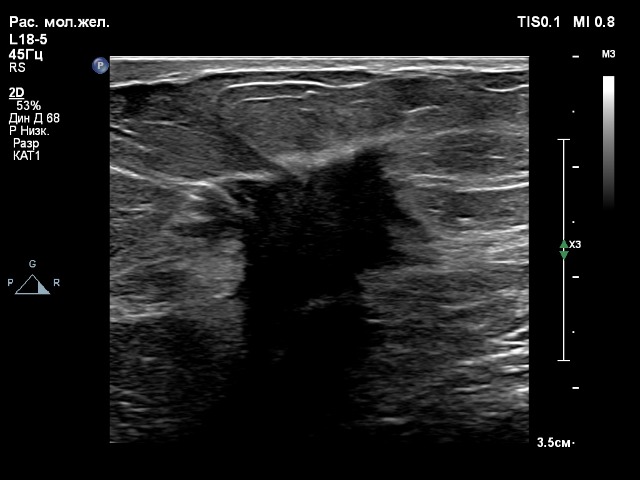

2. Датчик eL18-4

- вены нижних конечностей для датчиков L12-3 и eL18-4;

Глубина сканирования одинаковая, 5 см.

Если покупать один линейный датчик, то тогда это eL18-4.

Очень мне понравился. Он прекрасно работает и на низких частотах с достойной картинкой сосудов, и на высоких частотах (щитовидная, молочные железы, мягкие ткани). У аппарата 4 активных порта, 4 датчика - ничего не надо переставлять. Это очень удобно. И тут датчик eL18-4 выполняет свою работу на 100%.

По картинке больше всего понравился eL 18-4, оба случая. Но на вкус и цвет, как говорится)

Компрессионная эластография данного образования молочной железы на датчике eL18-4 получилась быстро и качественно, а на датчике L18-5 хуже получалась, индикатор качества не поднимался до верха, что указывало бы на высокое качество эластограммы, которую можно оценивать. На датчике eL18-4 можно сказать влёт.